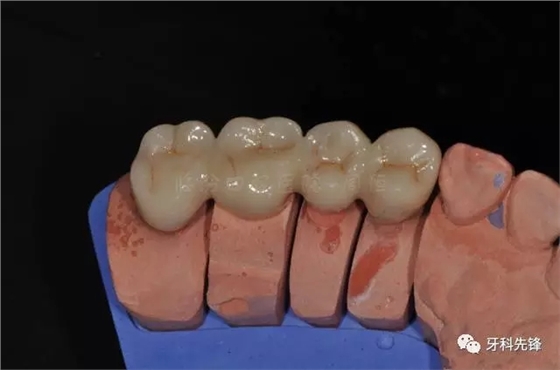

圖25烤瓷冠頜面觀

640.webp (29).jpg